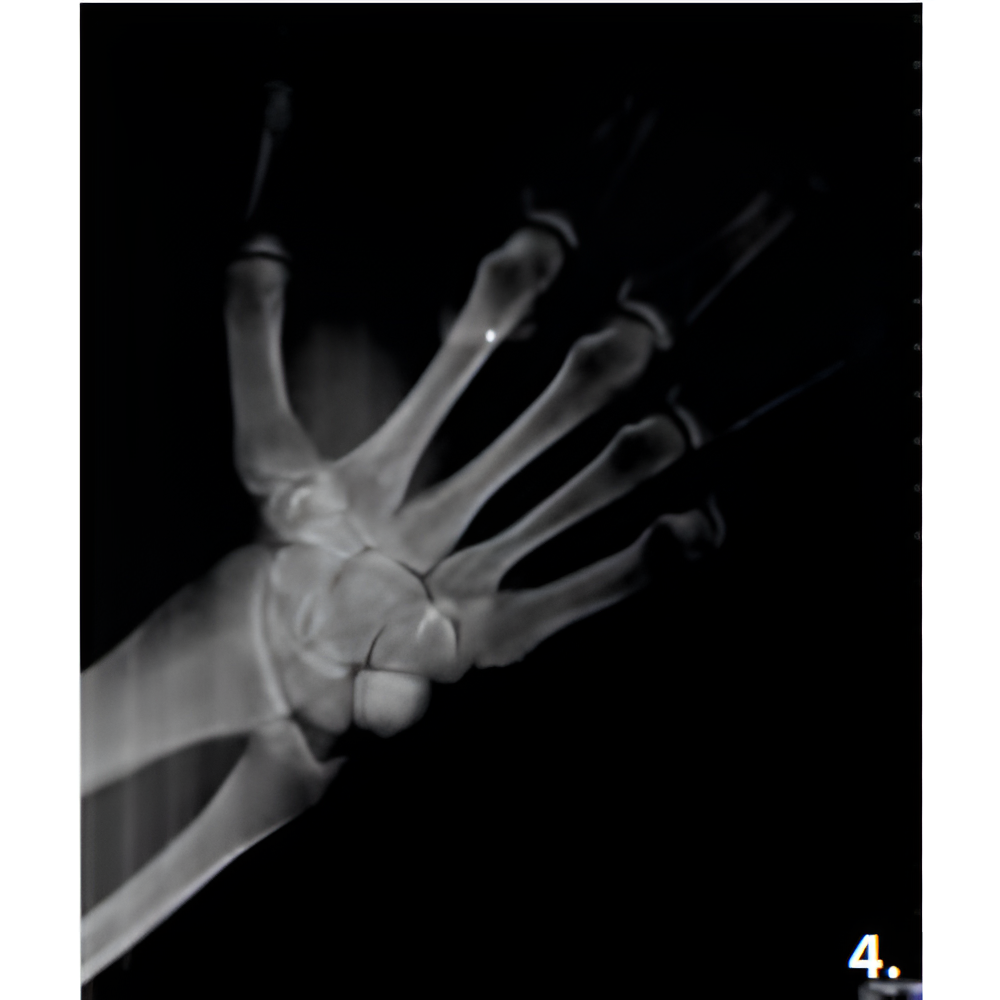

Hyperion X9 pro meets every diagnostic requirement by easily integrating into the work flow and guaranteeing maximum comfort for both patient and operator. SuperHD quality images that allow the doctor to make a correct diagnosis, thanks to easy and completely guided procedures. Full accessibility and user-friendliness with the innovative full-touch control panel and fast Face To Face positioning which guarantees maximum comfort to both patient and operator.

- Field Of View: 4x4, 6x6, 10x8, 13x16

- Multi FOV

- Focused FOV

- Medium FOV